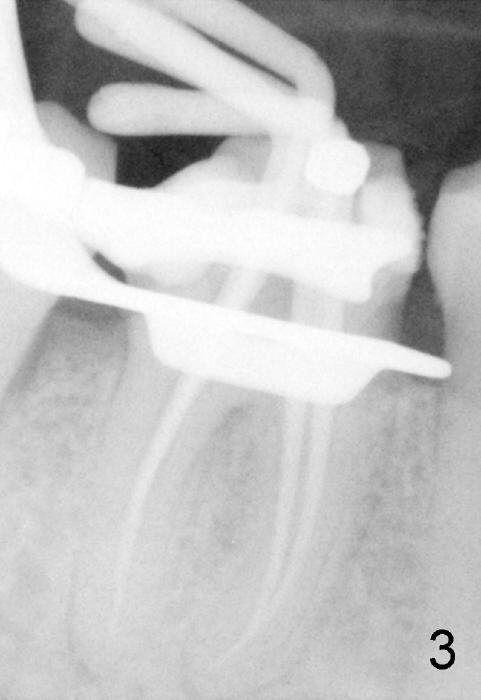

Dowman太太来自德国,收入不好,抽烟,不用牙线,结石多(图一箭头),右下第一磨牙远中龋齿(*)。她深洗还积极(图二已经没有明显结石),处理龋齿拖拖拉拉,九个月后,去龋时穿髓,暂封(图二*),她的后牙牙根特长,说明什么?下面回答。不得不做根管治疗(图三),图四是根管治疗后一年半拍摄,虽然根尖有阴影(箭头),但是病人没有任何症状。又过两年多病人主诉右下不适,根尖片显示根分叉阴影特大(图五*),近中根近中也有阴影(箭头),这时结石又出现。口内检查太容易了:右下第一磨牙颊侧有瘘道(图六双箭头),颊侧根分叉上皮附着失去(图六单箭头,也就是牙周袋深,探测出血),而舌侧根分叉牙周袋正常。总之,近中根有隐裂,接近颊侧,而远中根好像不容易出事,因为它比近中根粗。当我们为她牙齿惋惜时,老外比较爽快,说“It is not your fault. I love eating nuts. I grind my teeth at night. My night guard is too old to wear”。这段话可能说明为什么她后牙牙根长。